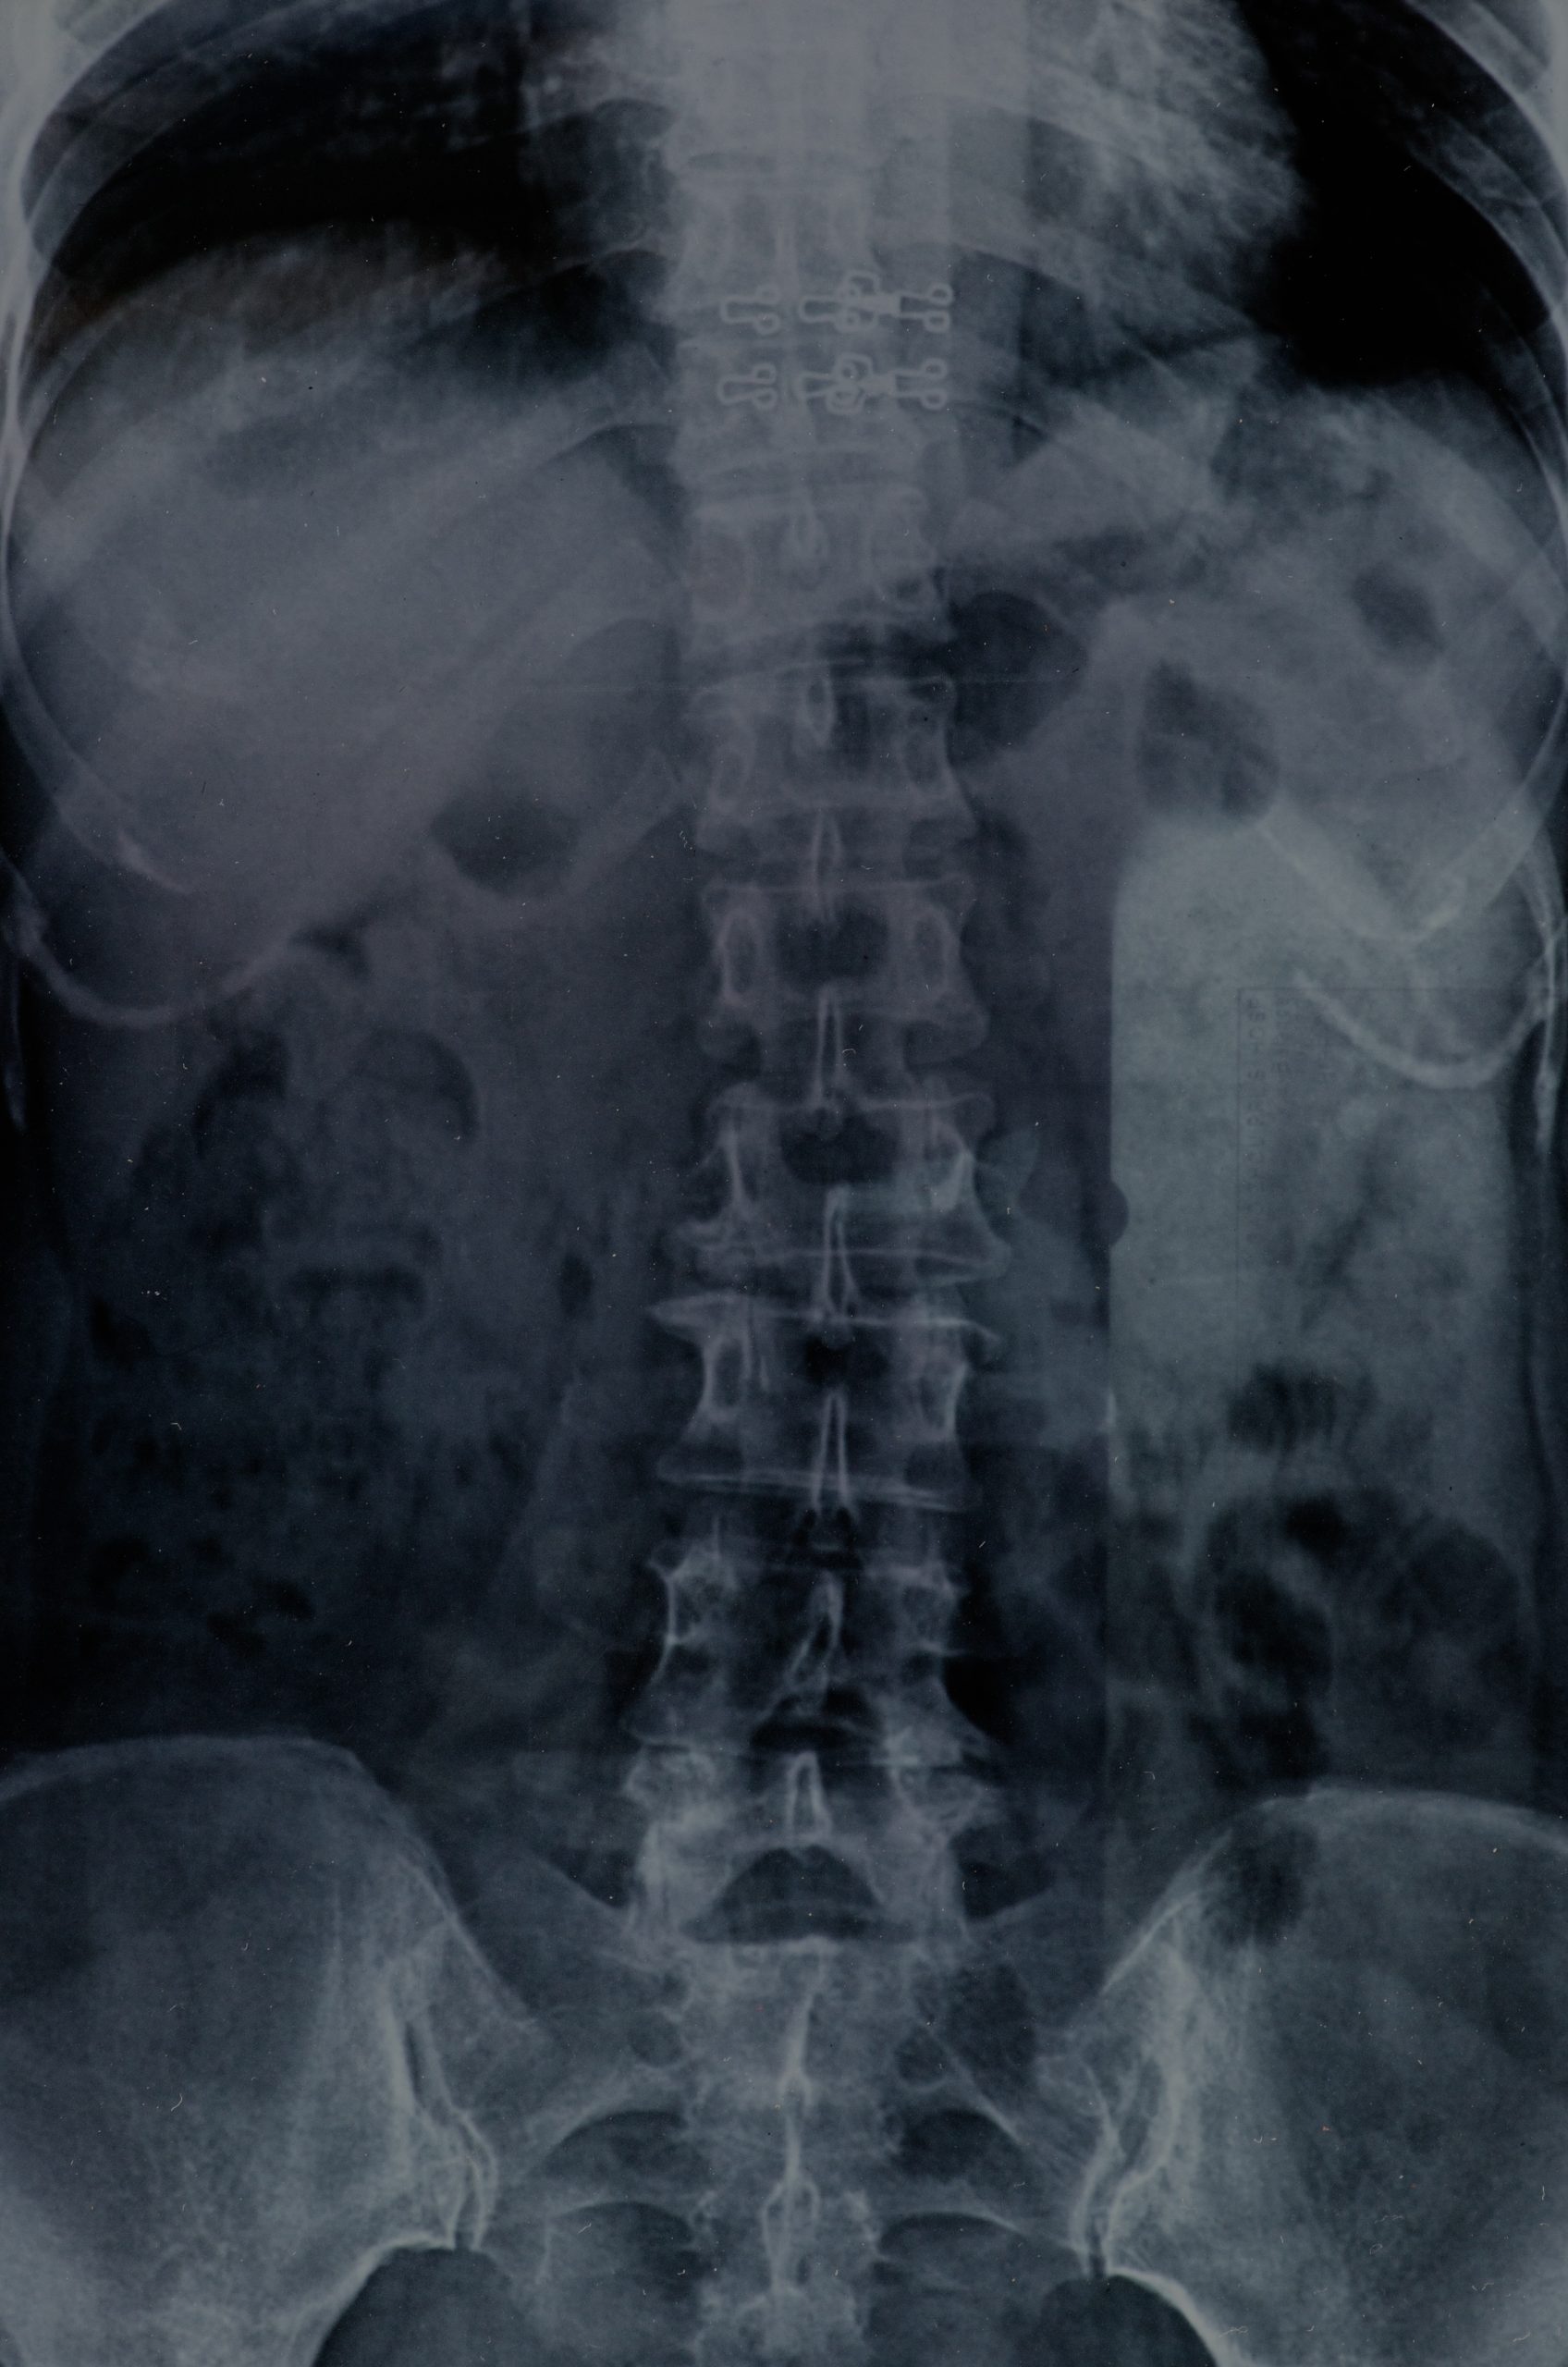

The mechanism of a pain pump is straightforward yet ingenious. The device comprises two main parts: the pump and the catheter. The pump is a programmable, battery-powered device that stores and delivers medication. It is surgically implanted under the skin of the abdomen. The catheter is a small, flexible tube that extends from the pump to the intrathecal space, ensuring direct delivery of pain relief medication.